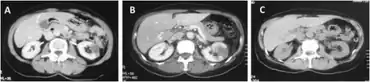

Drug induced vasculitis-a)An ischemic area in left kidney b)increasing of left renal ischemia tissue and novel ischemia right kidney c) after one year reduction of ischemic areas in both kidneys